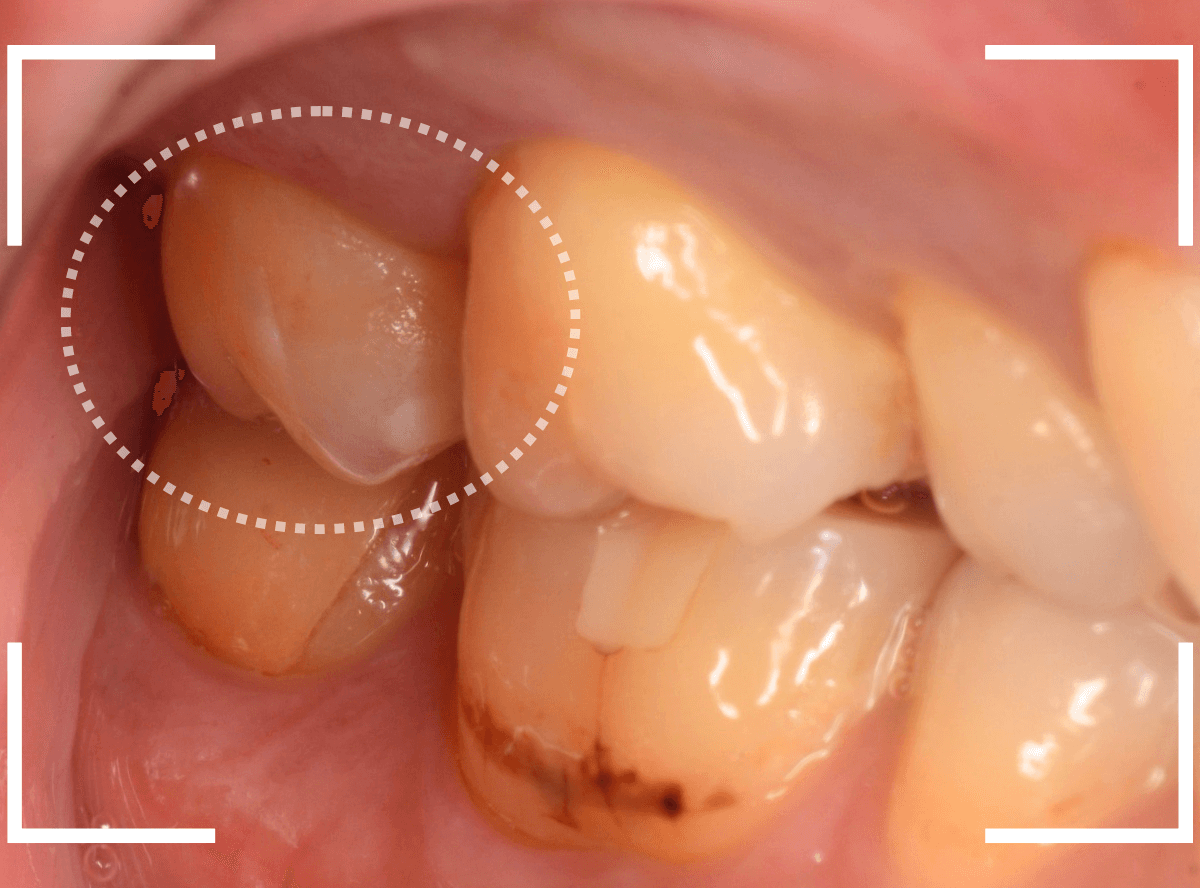

舌のそばの虫歯とセラミック治療

下の奥歯が虫歯になった患者さんのケースです。

〇部が虫歯の部分です。

写真で見てわかるように、常に舌が歯に触っているような状況です。

このような場合、虫歯を見つけづらいですし、治療の難易度もあがります。

虫歯の治療を開始します。

隣の歯とのすき間を中心に広い虫歯になっていました。

虫歯治療後、特に症状もなく経過観察できましたので、つめものを作る治療に入ります。

セラミック治療をご希望されましたので、

小臼歯をE-MAX・インレー、

大臼歯をジルコニア・インレーで処置することになりました。